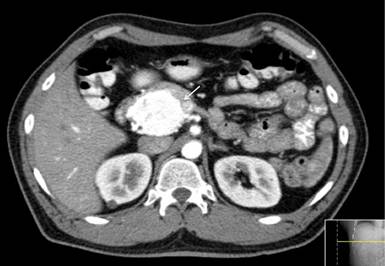

Ultrasound of the upper abdomen revealed a 5 cm hypoechoic lesion of the head of the pancreas. No dilation of the bile ducts was noticed. Computerized tomography with cross sectional imaging of the abdomen revealed a 6.1x5.4 cm lesion in the head of the pancreas. The lesion was enhanced in early arterial phase (Figure 1) and washout during the portal phase. The lesion did not cause dilation of neither the intra- nor extra-hepatic bile ducts. Although the tumor displaced the superior mesenteric artery and the portal vein, there was a clear plane between the lesion and the vasculature. Endoscopic ultrasound revealed the aforementioned lesion with no vascular involvement. Due to the extreme hypervascularity of the lesion it was elected not to biopsy the tumor.

|

Figure 1. Computerized tomography in early arterial phase showing a hypervascular lesion of the head of the pancreas (white arrow). |